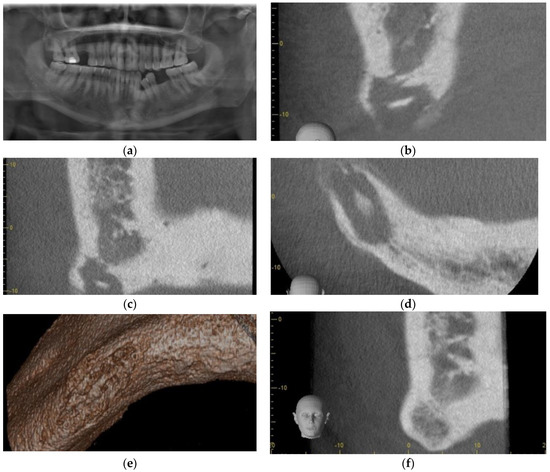

3.3. Case 3